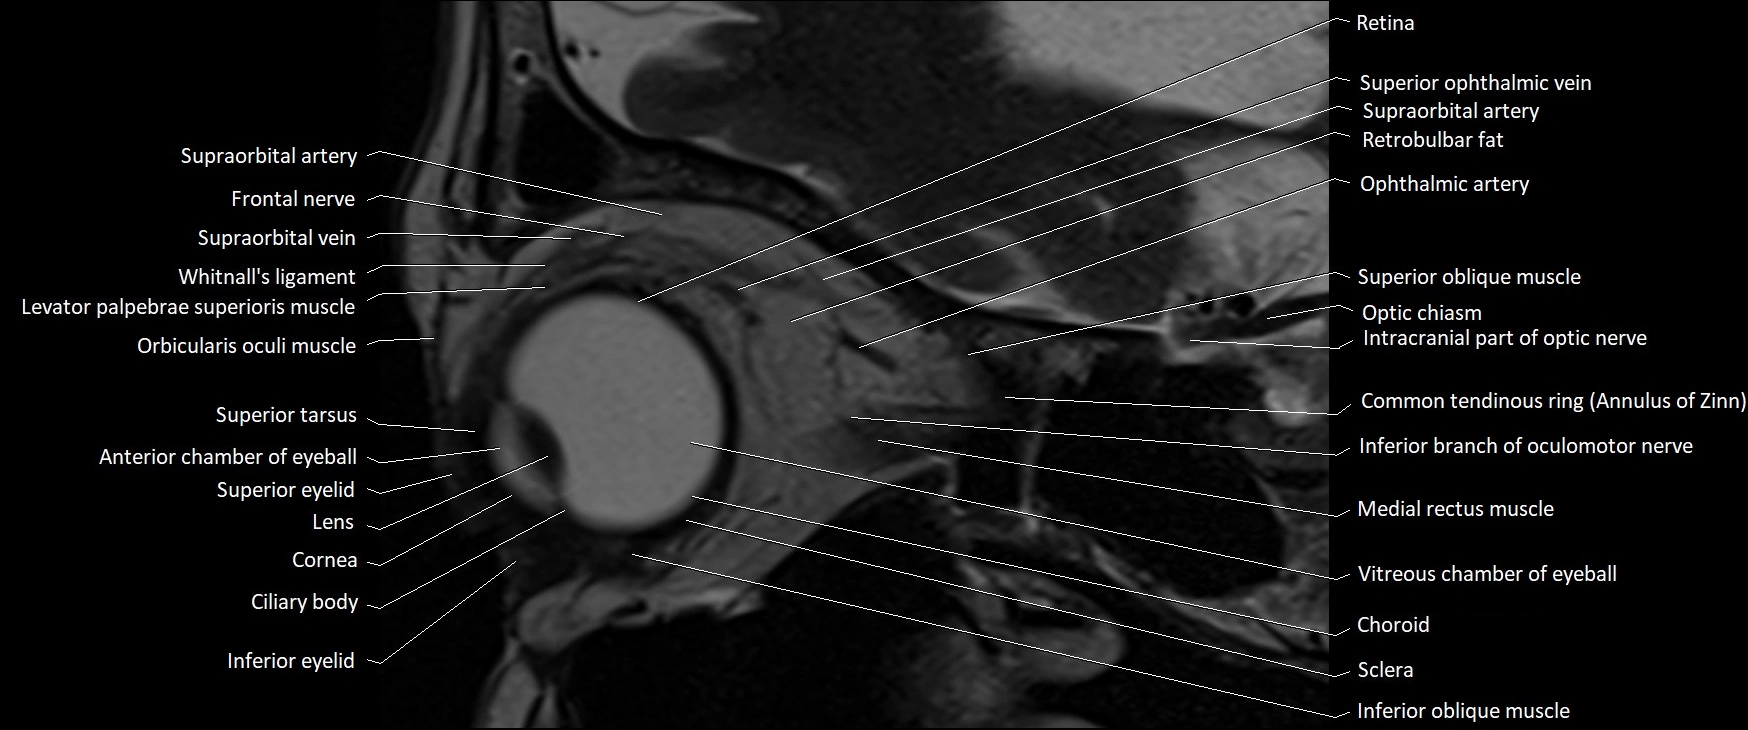

- Anterior chamber of eyeball

- Choroid

- Common tendinous ring (Annulus of zinn)

- Cornea

- Inferior eyelid

- Inferior oblique muscle

- Infraorbital nerve

- Intracranial part of optic nerve

- Levator palpebrae superioris muscle

- Optic chiasm

- Orbicularis oculi muscle

- Posterior chamber of eyeball

- Retina

- Retrobulbar fat

- Sclera

- Superior eyelid

- Superior oblique muscle

- Superior ophthalmic vein

- Superior tarsus

- Supraorbital artery

- Supraorbital vein

- Vitreous chamber of eyeball

- Whitnall's ligament

MRI images